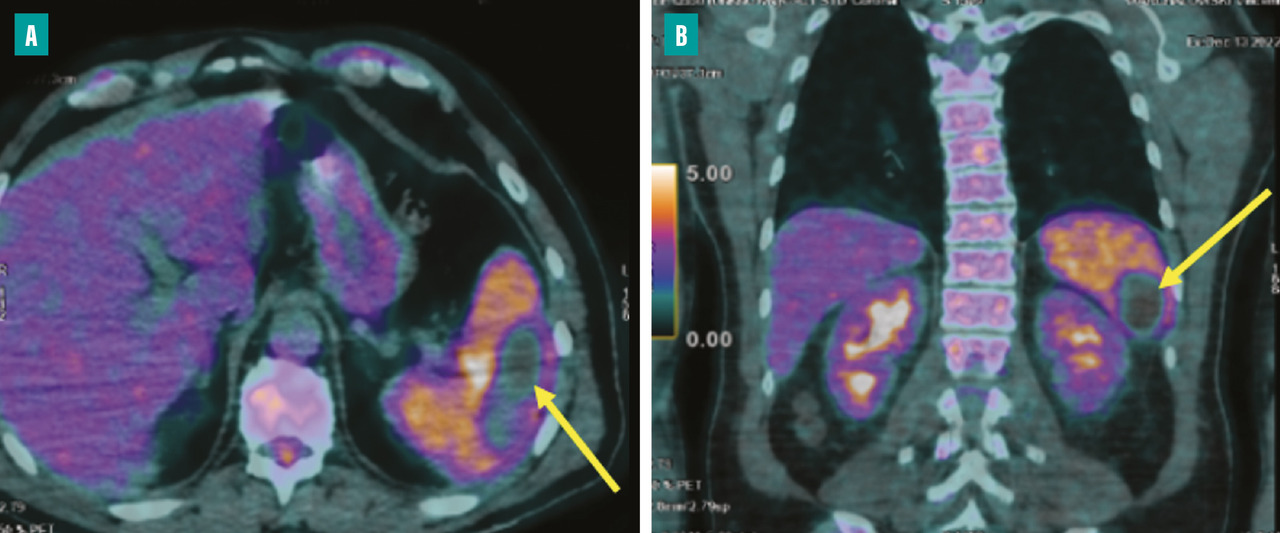

Complications spléniques

C’est la deuxième localisation embolique de l’EI, son incidence est variable entre 28 et 35 %.8,9 L’embole obstructif de l’artère splénique entraîne un infarctus splénique qui peut s’infecter ou s’abcéder. Cette embolisation est souvent silencieuse, découverte sur le scanner ou le TEP-scan (fig. 6 ). L’apparition d’un syndrome fébrile fait craindre un abcès splénique. Le traitement de l’abcès splénique est habituellement conservateur, mais en présence d’un abcès volumineux, une ponction sous scanner est discutée. La chirurgie est réservée aux ruptures de l’abcès.

En cas de sepsis non contrôlé, il est impératif de refaire des hémocultures, de réaliser une surveillance rapprochée en ETT et en ETO, à la recherche d’un abcès périvalvulaire ou périprothétique. Un scanner thoraco-abdomino-pelvien et cérébral ou un TEP-scan est demandé, à la recherche d’un foyer infectieux embolique.